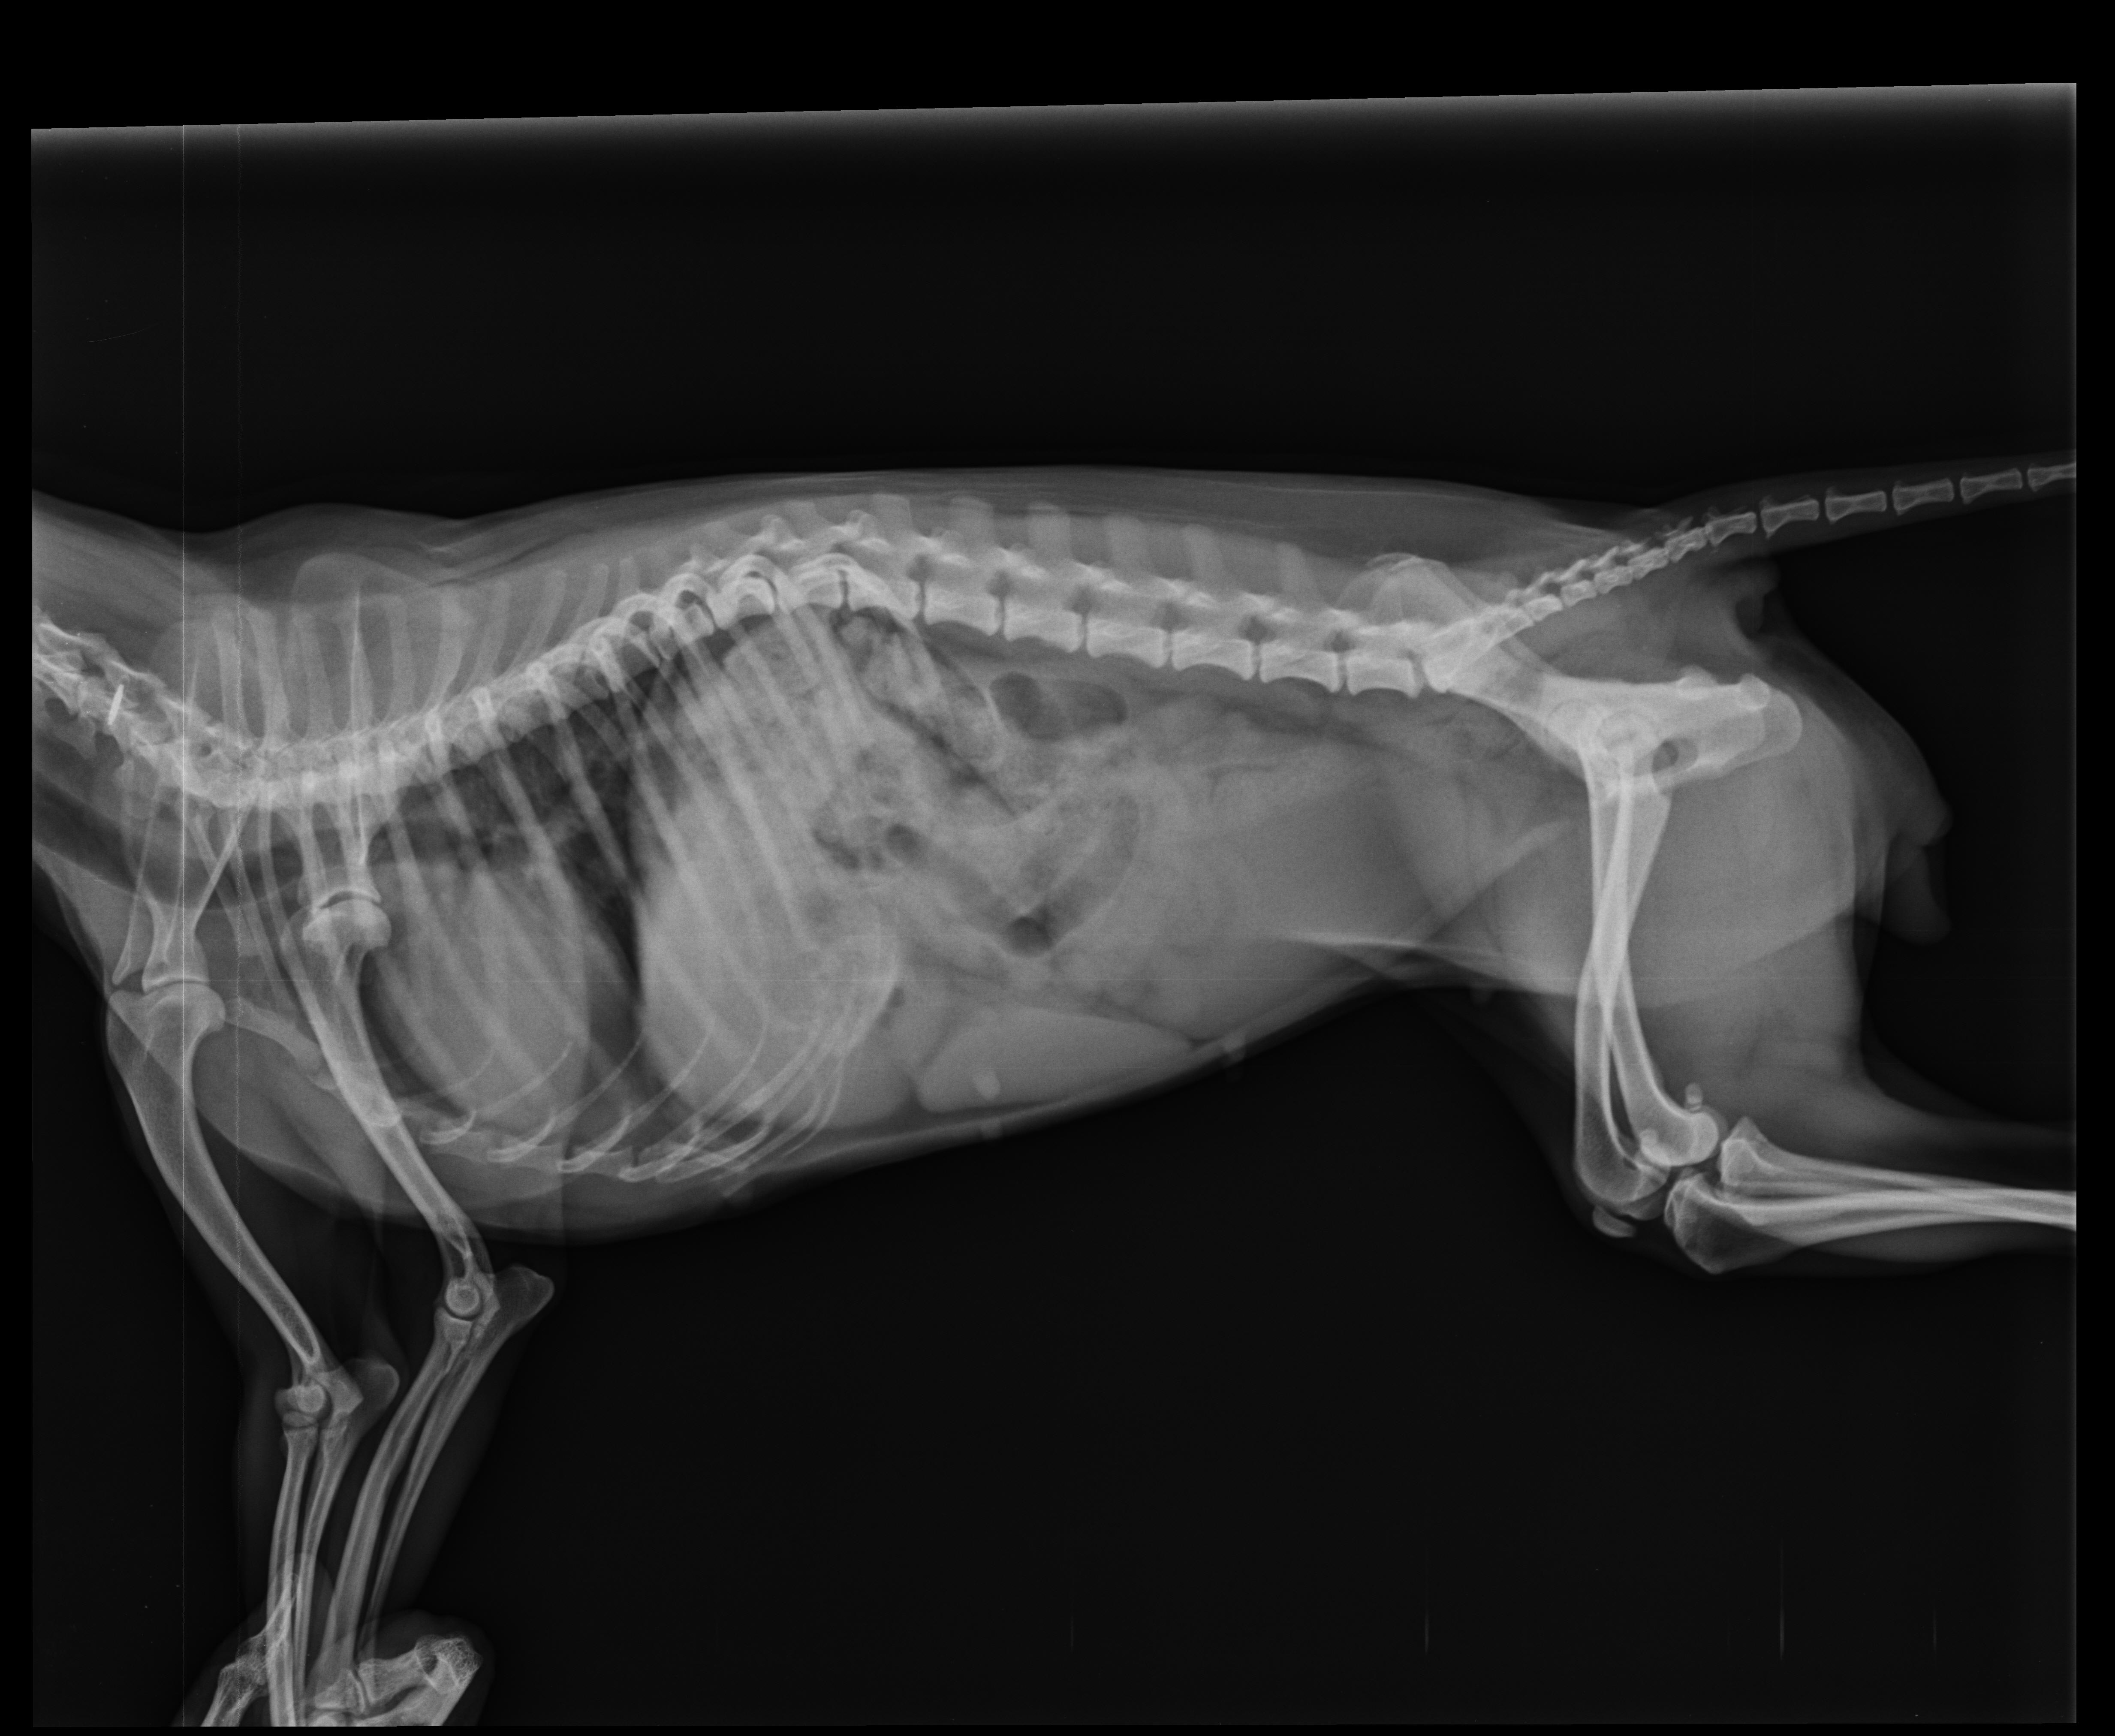

Pet's info: Dog | German Pinscher | Female | unspayed | 4 years and 7 months old | 9 lbs

4 years old female Pinscher. Since two days, she hasn't use rear left leg. Its happen suddenly. Our vet start to vitamin B, pain killer and cortisone. Also her appetite is fine. If you wish, i can sent the videos of her.

As there is no fractures, it's likely to be either a knee cap injury (patelar luxation) or a ligament condition (cruciate ligament tare). you should have the xrays sent to a radiology or orthopedic specialist, she will probably need to have a surgery done on that leg.